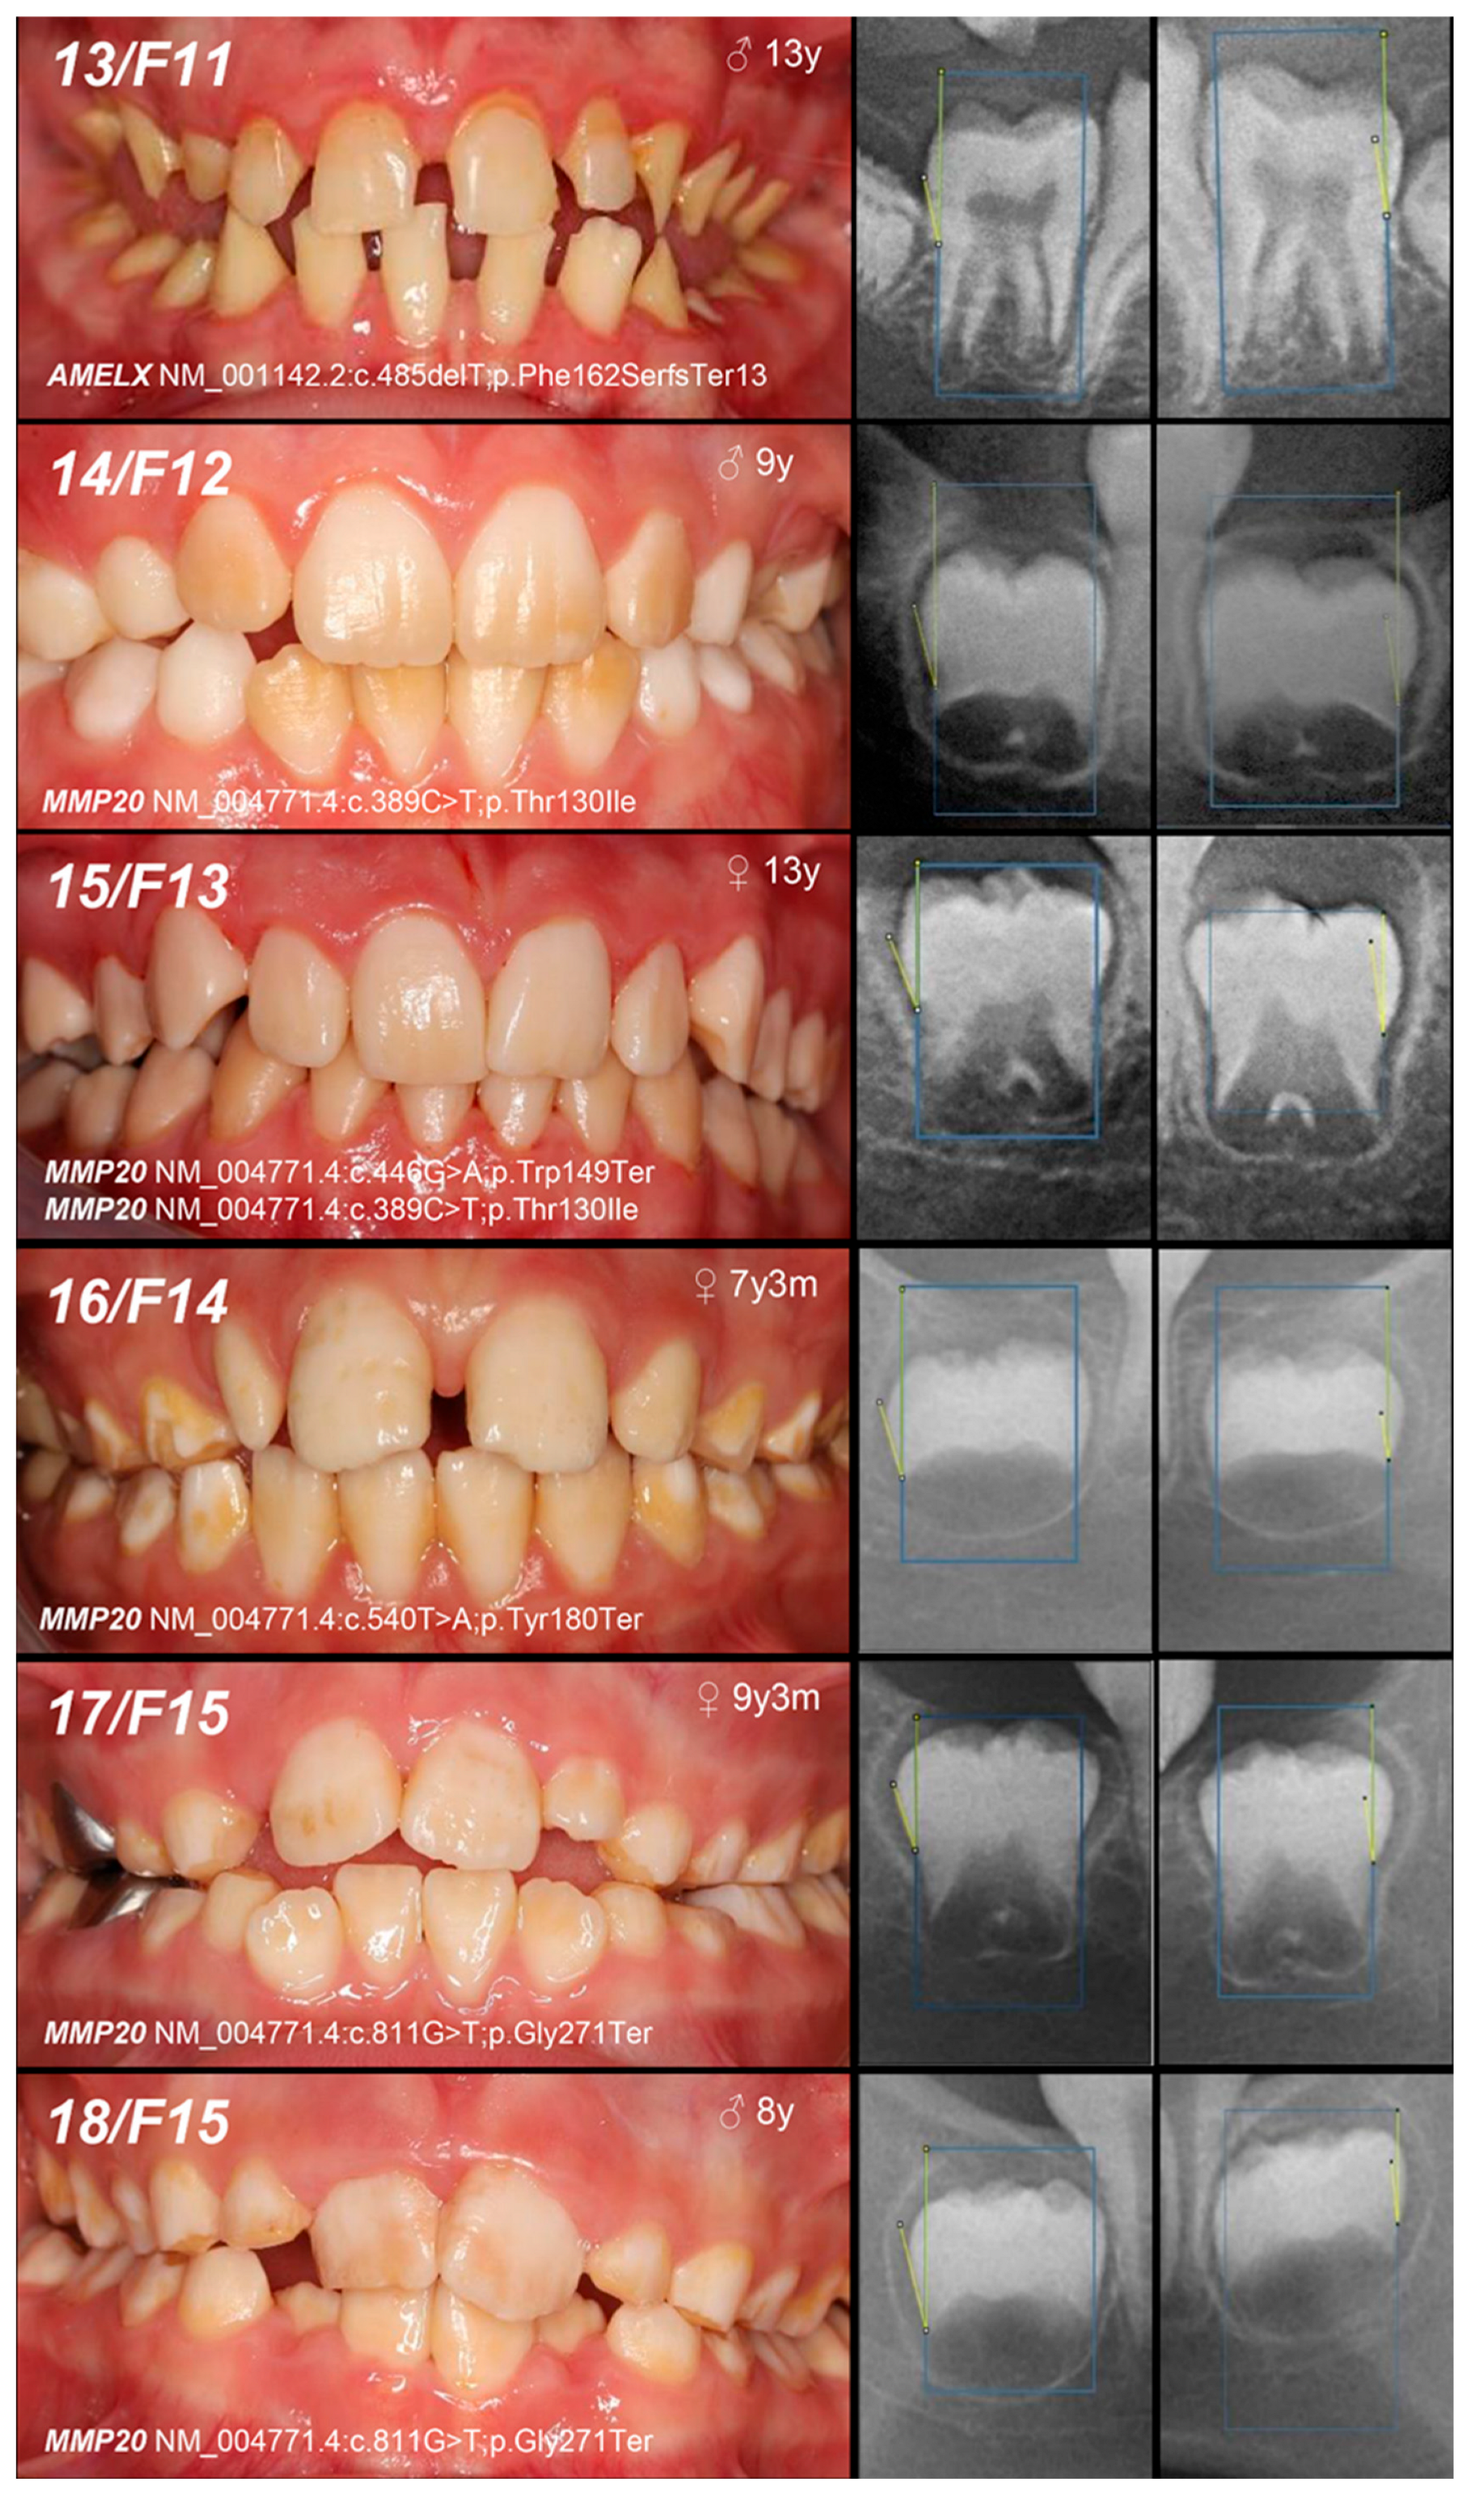

| Patient (n) Family (n) | Phenotype | OMIM, Mode of Inheritance, Gene Affected | Gene Variant | Zyg. | Protein Outcome | References | Fam. Segreg. | ACMG |

|---|---|---|---|---|---|---|---|---|

| 16, F14 | Hypomineralized (pigmented hypomature) | IIA2, AR, MMP20 | c.540T>A | +/− | p.Tyr180Ter | [28] | Mo (UC) Fa (U) | likely pathogenic (PVS1: very strong, PM2: moderate) GnomAD: 0.00000707 |

| 17, 18, F15 | c.811G>T | +/− | p.Gly271Ter | novel | Mo (AC) Fa (U) | likely pathogenic (PVS1: very strong, PM2: moderate) | ||

| +/− | ||||||||

| 19, F16 | +/− | Mo (UC) Fa (U) | ||||||

| 20, F17 | Hypoplastic (pitted) | IA, AD, LAMB3 | c.-132T>C | +/− | / | novel | Mo (AC) Fa (U) | VUS (PM2: moderate, BP7: supporting) |

| 21, 22, F18 | Hypomineralized (hypocalcified) | IIIA, AD, FAM83H | c.1669G>T | +/− | p.Gly557Cys | [29] | MoFa (NA) | benign (BA1: stand-alone, BS1: strong, BS2: supporting, BP4: supporting, BP6: supporting) * |

| +/− |